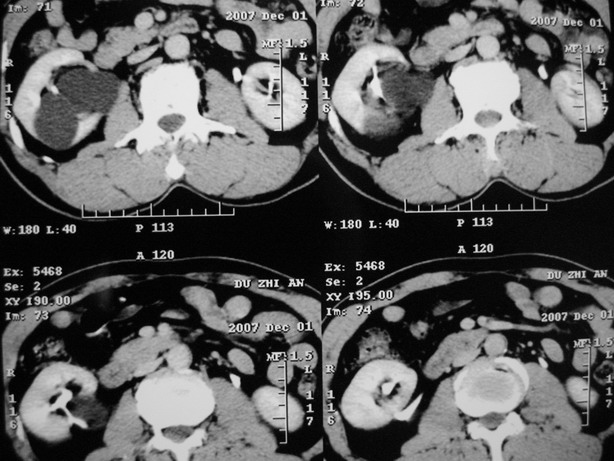

增强:

延迟期造影剂没有进入囊性病灶内考虑多发性肾囊肿,包括一个盂旁囊肿。

肾盂旁多囊性占位,有实性成分,增强有轻度强化,收集期病变内无造影剂显影。诊断肾盂旁囊肿,有实性成分无法解释,查书后诊断为:多房性囊性肾瘤!!不知大家同意否?????????对本病知道不多,望大家不吝赐教!!

囊间间隔强化与肾实质相仿,还是支持多发囊肿,定期复查

支持多发囊肿(所谓实质部分其实是肾实质)

右肾多发囊性低密度影,囊内有增强的隔及实性组织,考虑囊性肾癌。